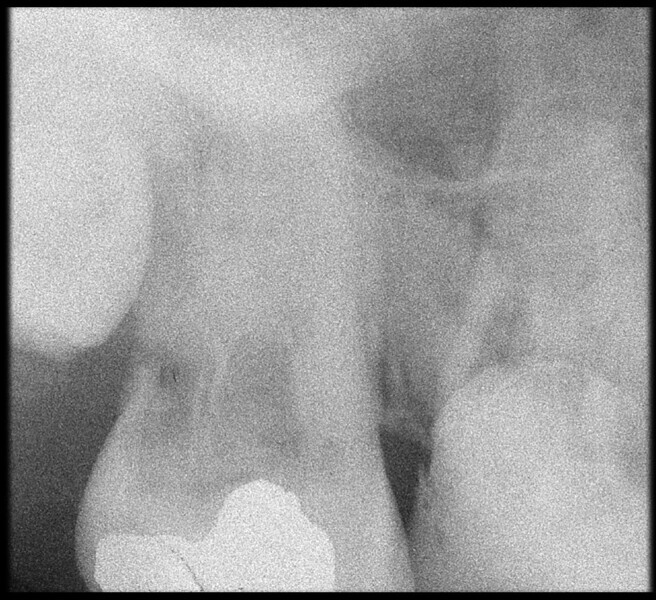

Use of 3D technology in the diagnosis and treatment of endodontic disease